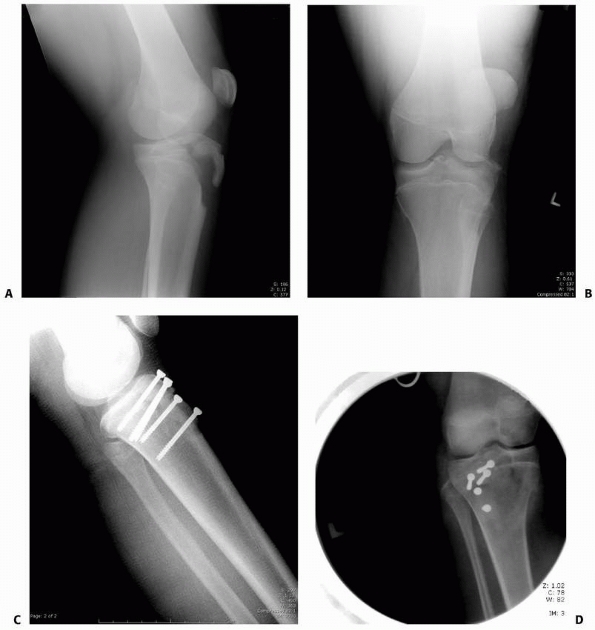

FIGURE 23-16 Five-year-old boy hit by car with fracture of the distal femur. A. AP radiograph of minimally displaced Salter-Harris type IV fracture of the distal femur. B.

AP radiograph of healed fracture. From this view, it is difficult to determine if injury to the physis has occurred, though a central growth arrest was suspected. C. MRI shows a central growth plate injury probably did occur, although this did not result in formation of a bony bar or growth arrest. (Courtesy of Robert Kay, MD, Los Angeles, CA.) |

epiphyseal fracture is growth disturbance with angular deformity or

shortening. This has been reported in 35% to 50% of patients regardless

of anatomic reduction.3,44,53,71,89,154,159

Salter-Harris types I and II fractures in other areas of the body

usually have a low risk of growth arrest, but even minimally displaced

fractures in the distal femur should be followed closely for growth

arrest (see Fig. 23-16) Growth disturbance is uncommon in patients younger than 2 years of age due to the flat shape of the physis in this age group.133